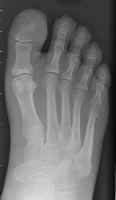

The above images show both the pre-operative and post-operative left foot of the same

patient. The pre-op film demonstrate osteomyelitis of the distal first phalanx that

was treated with a great toe amputation.